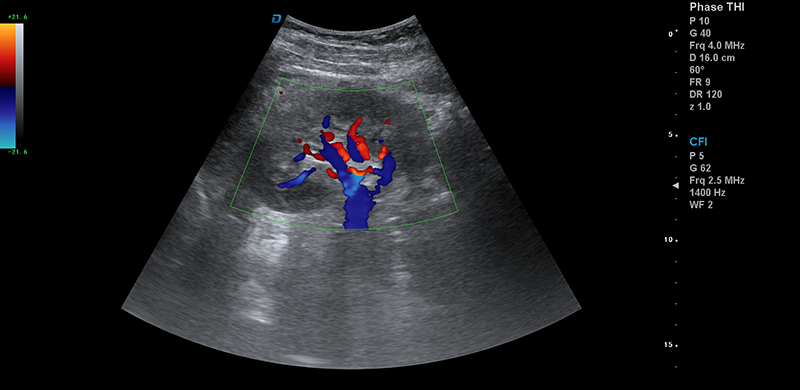

DW-T8四維彩超機

可滿足婦產科心臟腹部、泌尿科、小器官、心血管、肌肉骨骼、兒科及新生兒等多系統的臨床診療需求。是一款性價比高的四維彩超

肝臟靜脈血流

頸動脈血流

彩超機心臟檢測圖

心臟

彩超機腎臟血流檢測圖

腎臟血流